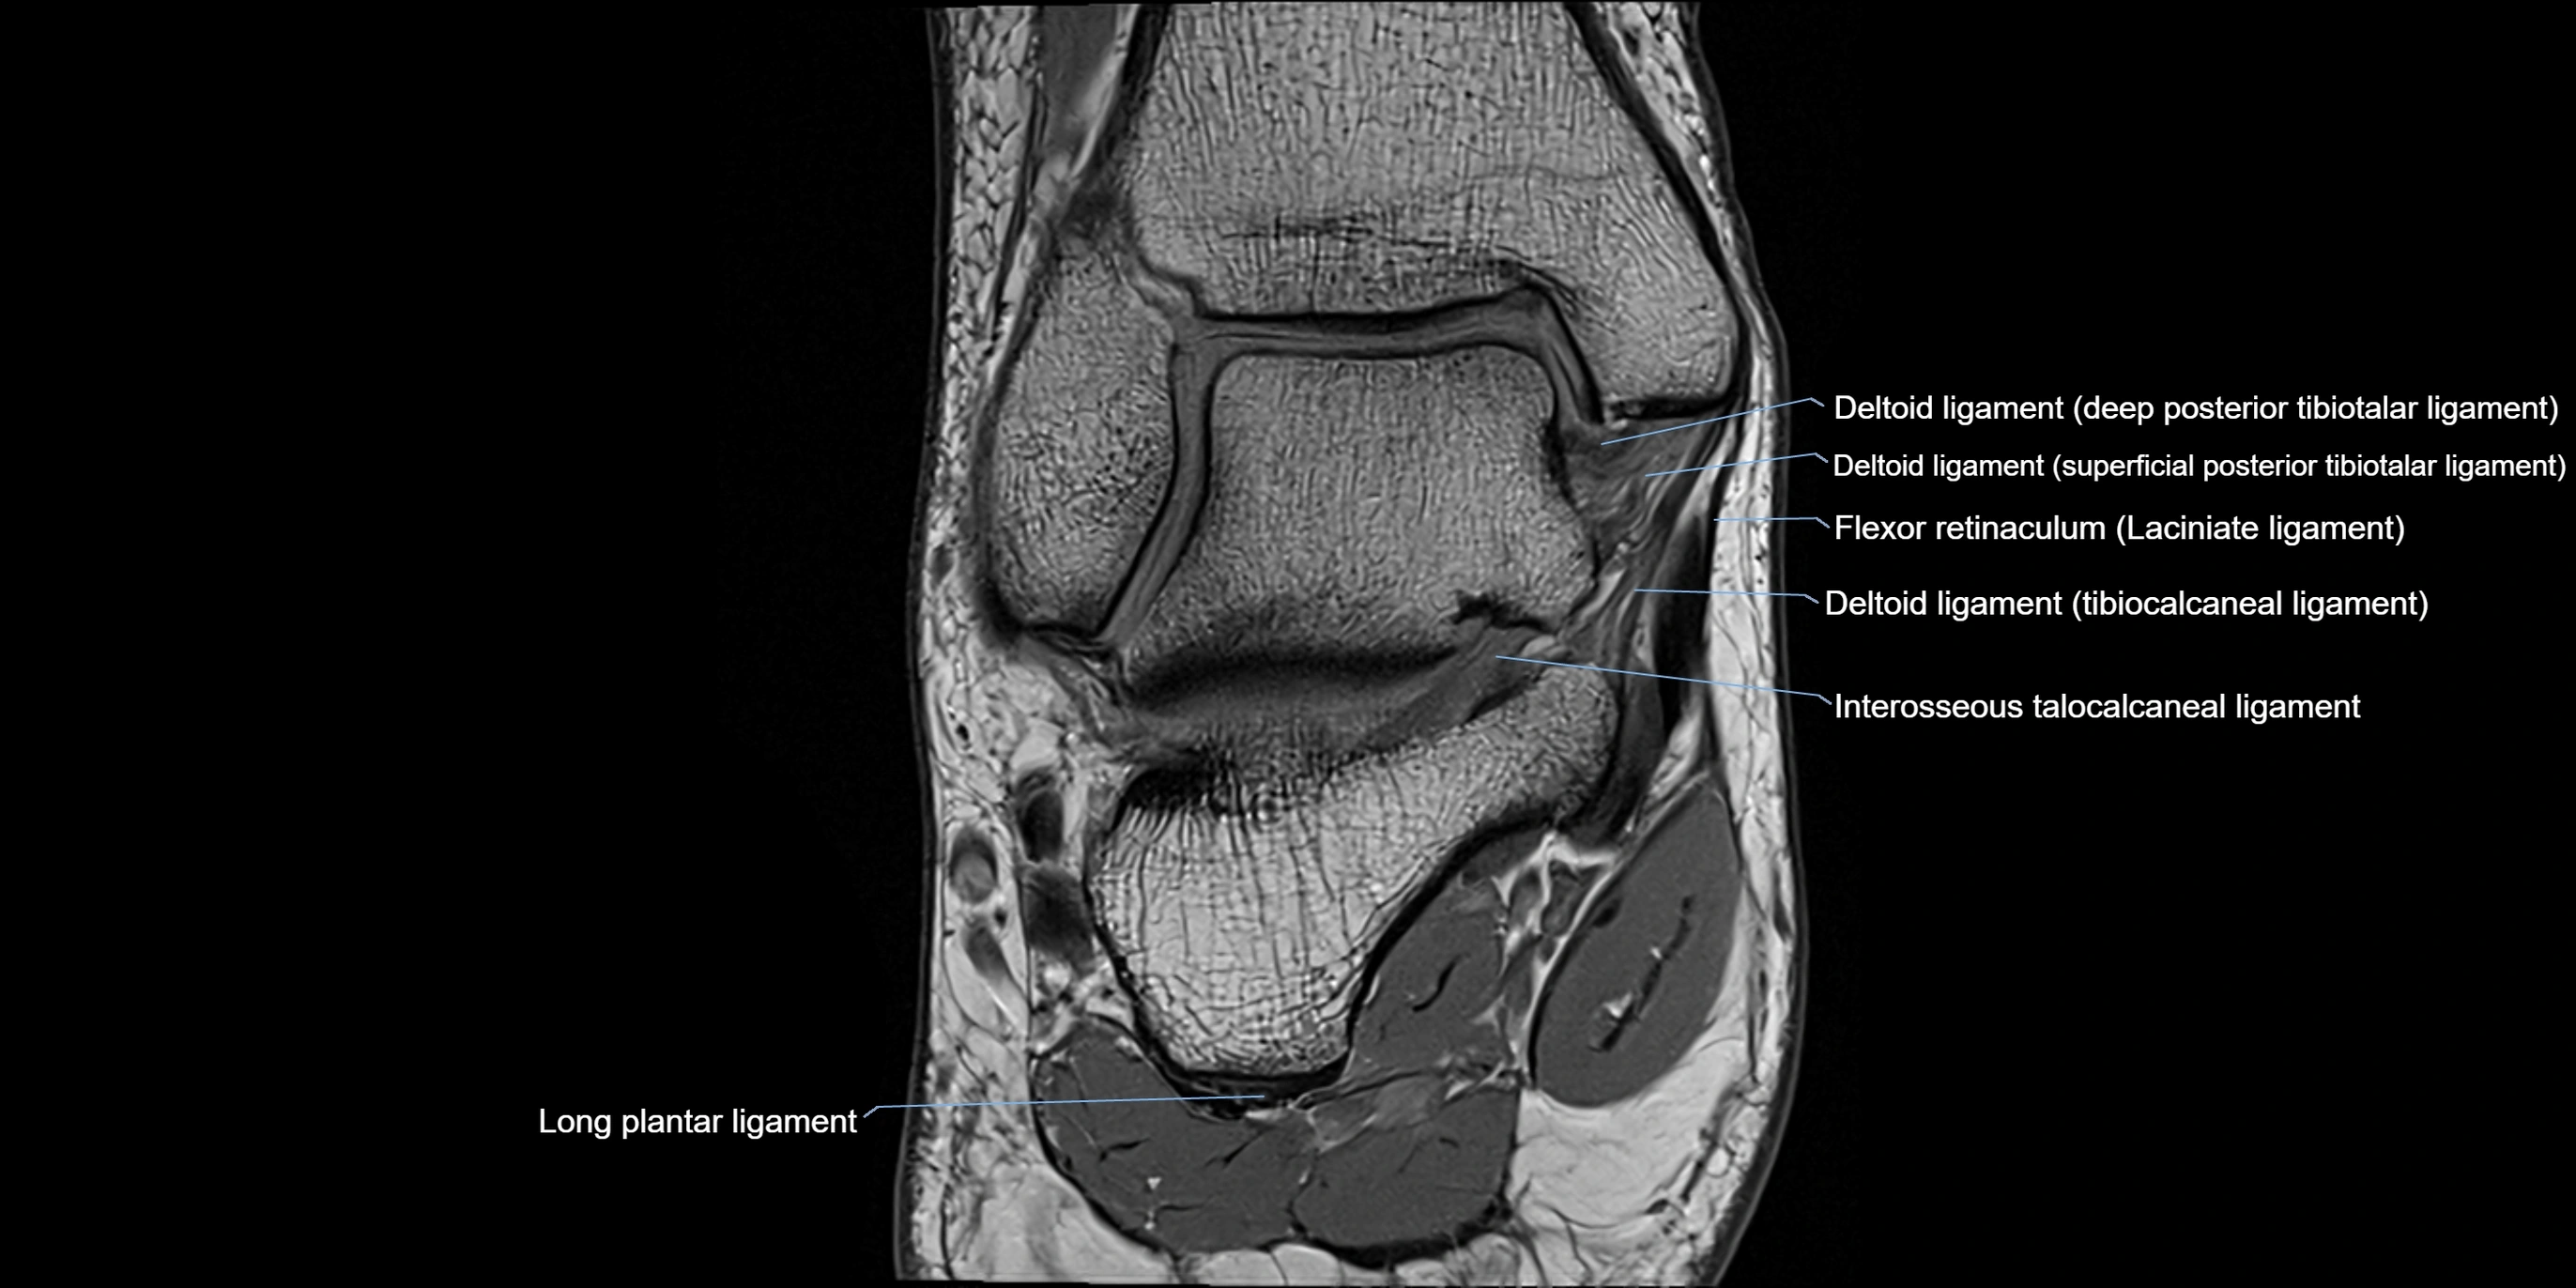

MRI image

image